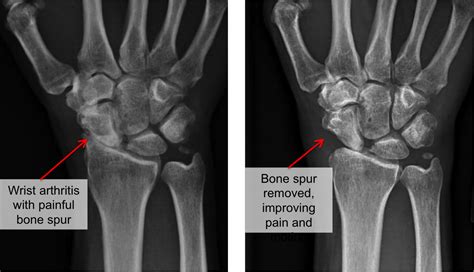

When you visit a specialist, they will likely start with a physical examination, checking for tenderness and testing your range of motion. To confirm a bone spur wrist diagnosis, medical imaging is necessary. An X-ray is the gold standard for visualizing bony projections, while an MRI may be used if the doctor suspects the spur is affecting soft tissues like tendons or ligaments. In some cases, an ultrasound might be used to examine how the spur interacts with moving parts of the wrist during real-time movement.

If conservative treatments fail to provide relief after several months, or if the bone spur is causing significant nerve entrapment—such as chronic carpal tunnel syndrome—surgical removal might be considered. This procedure, often called an osteophyte excision, involves removing the bony growth to relieve pressure on the joint and surrounding nerves. With modern arthroscopic techniques, this is often performed as a minimally invasive procedure, leading to shorter recovery times and less scarring compared to traditional open surgery.